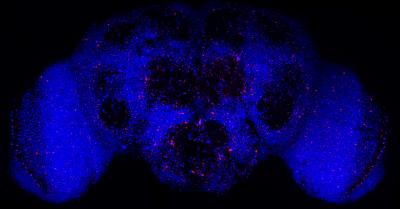

image: Neurons in red are the unfit neurons that will be killed for the better functioning of the whole brain, marked in blue.

For the first time, scientists at the Champalimaud Centre for the Unknown (CCU), in Lisbon, Portugal, have shown that neuronal cell death in Alzheimer's disease (AD) may actually not be a bad thing - on the contrary, it may be the result of a cell quality control mechanism trying to protect the brain from the accumulation of malfunctioning neurons. Their results, which were obtained using fruit flies that had been genetically modified to mimic the symptoms of human AD, were published in the journal Cell Reports.

The cell quality control mechanism at play is called cell competition. It leads to the selection of the fittest cells in a tissue by enabling a "fitness comparison" between each cell and its neighbors - with the fitter cells then triggering the suicide of less fit ones.

The first thing the scientists wanted to do was to see whether in these flies, neuronal death was indeed activated by the process of fitness comparison - in other words, "that the neurons were not dying on their own but being killed by fitter neighbors", Moreno points out.

This means that the anti-aging mechanism in question keeps working well in Alzheimer's disease and shows that, in fact, "the neuronal death protects the brain from more widespread damage and therefore the neuronal loss is not what is bad, it is worse not to let those neurons die", Moreno emphasizes. "Our most important finding is that we have probably been thinking the wrong way about Alzheimer's disease. Our results suggest that neuronal death is beneficial because it removes neurons that are affected by noxious beta-amyloid aggregates from brain circuits, and having those dysfunctional neurons is worse than losing them" Moreno concludes.